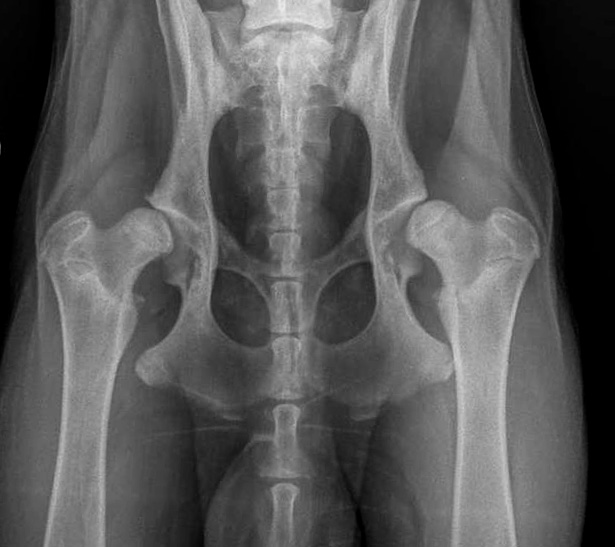

![]() HD fast-normal / HD-B / HD-1 |

B |

= Übergangsform |

HD-1 |

fast-normal |

Fast normal, geringe Veränderungen an Kopf oder Pfanne, NORBERG-Winkel von mindestens 100 Grad |